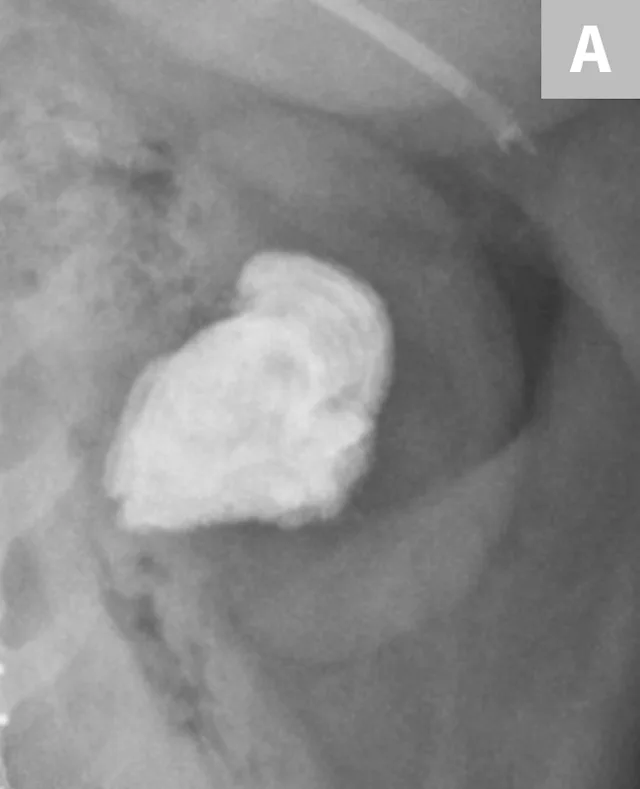

FIGURE 8A

1 / 4

Lateral radiograph of the urinary bladder in a dog with a confirmed calcium oxalate calculus. This calculus has a very irregular margin often seen with calcium oxalate calculus formation.